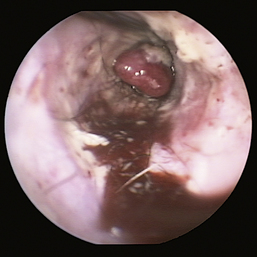

The middle ear consists of an air-filled tympanic cavity, three auditory ossicles, and the tympanic membrane. The tympanic membrane is located at a 45-degree angle in relation to the central axis of the horizontal part of the external ear canal. The tympanic membrane is a semitransparent membrane that separates the external ear canal from the middle ear, is thin in the center and thicker at the periphery, and is divided into two sections, the small upper pars flaccida and the larger lower pars tensa (Figure 20-2). The pars flaccida is the pink, small, loosely attached region forming the upper quadrant of the tympanic membrane that contains small blood vessels. The pars flaccida is usually flat; however, even in the healthy ear one may identify a bulging pars flaccida (Figure 20-3). The exception is the Cavalier King Charles Spaniel, in which a bulging pars flaccida may be indicative of a disease known as primary secretory otitis media (PSOM) (Figure 20-4).

image

Figure 20-3 Bulging pars flaccida in a dog without any external or middle ear disease. 1, Pars flaccida; C, caudal; D, dorsal; R, rostral; V, ventral.

(Courtesy of Dr. Lynette Cole, The Ohio State University, Columbus, Ohio.)

Figure 20-9 Bulging pars flaccida in a dog without otitis media. 1, Pars flaccida; C, caudal; D, dorsal; R, rostral; V, ventral.

Figure 20-10 Bulging pars flaccida in a Cavalier King Charles spaniel dog with primary secretory otitis media. 1, Pars flaccida.